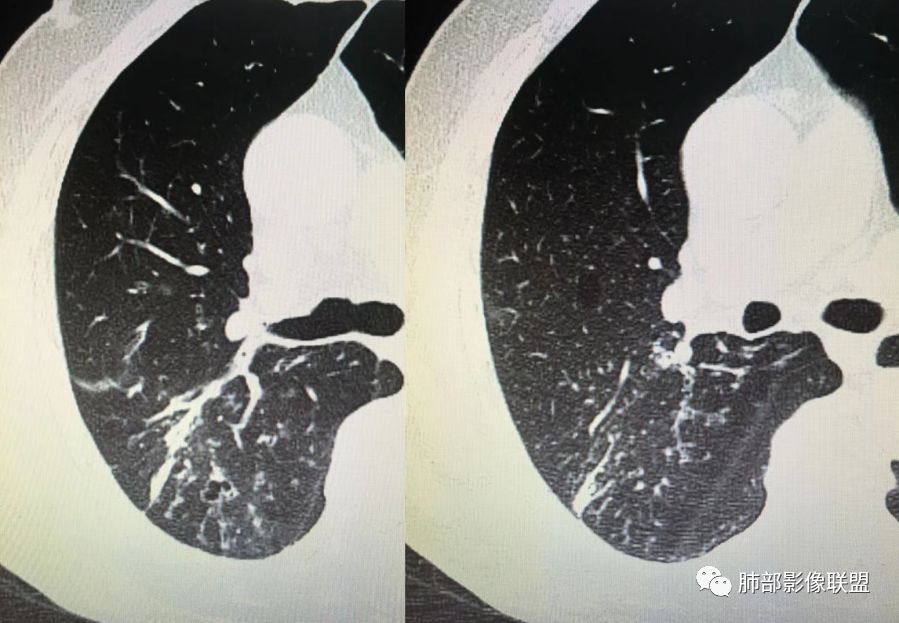

胸CT示病变位于右肺上叶,右肺上叶前段支气管壁不规则增厚狭窄、远端扩张。右肺上叶后段实变影,纵隔窗实变内可见钙化灶,可见支气管引流征,引流支气管壁明显增厚,边缘可见短硬毛刺,胸膜牵拉,u型征,周围可见卫星灶,并可见支气管扩张及其管壁增厚;病灶整体存在膨胀性生长。考虑良性病(结核)变基础上合并癌变,腺癌?

患者中老年男性,咳嗽喘息半年。查体双肺闻及哮鸣音。胸部CT:右肺上叶后段不规则结节灶,可见长毛刺、胸膜牵拉、分叶及钙化征象,周围见点片状卫星灶,近端支气管壁增厚,呈支气管爬行征。综合考虑结核。鉴别恶性病变。

右上肺的占位,毛刺,凹陷,总体偏恶性,但周围卫星灶,考虑腺癌可能性最大,结核也不能排除。

老年男性,咳嗽半年,右肺上叶后段实性结节伴粟粒状卫星灶,结节内有钙化,部分边缘平直,周围见长索条,有胸膜牵拉,结核是明确的,常规需要增强判断有无合并肺癌,当然该患者已经穿刺。

右肺上叶后段结节,点状钙化,边缘见细长毛刺,胸膜凹陷,卫星灶伴树芽症,支气管壁增厚扩张,有截断,考虑结核,但腺癌没法排除,确实有增强就基本能明确。

右肺上叶后段实性结节伴卫星灶,结节内有钙化,部分边缘平直,长索条,胸膜牵拉,考虑结核,但恶性征象还是有的,需除外腺癌!

右肺上叶后段不规则结节,长毛刺,卫星灶,斑点状钙化伴细小钙化,边缘部分平直,收缩力不强,倾向一元解释TB可能大,鉴别腺癌

右肺上叶病灶,可见分叶、毛刺、胸膜牵拉,周围见花花草草,似乎是卫星灶,考虑结核,鉴别腺癌。右肺支气管管壁增厚并扩张,考虑支扩,病史有喘息,哮鸣音,考虑合并有曲霉菌感染。综合考虑腺癌合并结核,曲霉感染。二元。

右肺上叶后段结节,长毛刺、钙化灶、近端小空洞、索条影、周围支气管树丫、引流支气管增厚,主体病灶侧后方分隔样空腔,弥漫支气管增厚,大气道受累,支持感染的征象较多,TB、曲霉;分叶、膨隆、脊状凸起、毛刺等恶性征象也有,遗憾没看到增强,只有期待活检一槌定音。

右肺上叶后段结节,呈不规则状,内可见钙化,边缘可见长短不一毛刺及胸膜牵拉,并可见分叶,邻近支气管管壁增厚,周围可见多发点状及结节状高密度影,首先考虑结核。

老年男性,咳嗽半年,右肺上叶后段实性结节,内见钙化,边缘部分膨隆,有长短毛刺、分叶、空泡征,胸膜侧见胸膜牵拉,周围不干净,见小卫星灶,右上叶后段支气管管壁增厚,扩张,有炎性及恶性征象,一元论常规考虑炎性肉芽肿病变,结核可能,腺癌不除外,二元结核并腺癌,建议增强及穿刺活检。

右上肺后段结节,边界清晰,可见分叶及毛刺,血管集束征,胸膜牵拉,内见斑点状钙化,周围见斑点状模糊影,同时伴支气管扩张,管壁增厚。整体感觉恶性征象多于良性,首先考虑肺癌,鉴别肉芽肿性病变,结核位置不像。

右肺上叶后段占位,毛刺,胸膜凹陷,病灶边缘内可见钙化、空泡,血管进入,病灶周围可见多发粟粒及树芽征,首先考虑肺结核;鉴别腺癌?鳞癌(周围小花、小草?)?

右上叶结节,毛刺、胸膜兔儿、空泡、钙化、血管,恶性征象不少,但是,可见沿支气管血管束分布的,周围可见卫星病灶,支气管扩张,外边胸膜是增厚的,结核可能性大。

中年男性,CT提示右肺上叶后段可见一结节影,可见长、短毛刺,胸膜牵拉,邻近支气管壁增厚,可见卫星灶,病灶内可见钙化,符合结核改变,腺癌待排。

右肺上叶后段团块影,内见钙化,周围胸膜有牵拉,近段支气管扩张管壁增厚,周围可见卫星灶,右支气管狭窄,综合考虑支气管内膜结核,鉴别真菌感染(气道侵袭性曲霉菌病)。

中老年男性,右肺上叶不规则团块状病灶,深分叶、长软毛刺,内部见空泡、多发钙化,相邻支气管增厚,考虑病变来源于气道,首先考虑结核,有空泡,这个腺癌多见,需要鉴别。

右肺上叶后段不规则结节,可见多发长毛刺,边界欠清,密度不均匀,其内可见斑点状钙化影,相应支气管壁增厚,管腔通畅,病灶周围见斑片状、斑点状稍高密度模糊影,考虑结核可能性较大。

中老年男性,右肺上叶不规则团块状病灶,深分叶、长毛刺,内部见空洞(近心侧)、钙化,相邻支气管增厚,有结核背景,首先考虑结核,腺癌需要鉴别。

右肺肿块,边缘平直,往下部分有膨胀感,毛刺、胸膜牵拉,内钙化,周围树芽,边界清,支气管壁增厚,考虑结核;不除外合并恶性。

右上后段结节,整体收缩,长软毛刺丶胸膜凹陷,有点状钙化丶小空洞,引流支气管明显管壁增厚,周边卫星灶明显,有喘息史半年,可能有应用激素史,致内源性复发,考虑TB,鉴别腺癌。

右肺上叶后段占位,分叶,毛刺,胸膜凹陷,病灶边缘内可见钙化、空泡,血管进入,病灶周围卫星灶,考虑肺结核合并肺癌。

不给增强图像,仅就形态判断,腺癌、结核都有可能。腺癌:分叶,毛刺,胸膜牵拉,近端支气管爬行结核:分叶,毛刺,胸膜牵拉,粗颗粒钙化散在分布,引流方向支气管壁增厚。这种情况通常放射科诊断不下结论:部位,病变,建议增强检查/穿刺活检。

3.本例病灶影像表现为:右肺上叶后段不规则结节灶,病灶整体存在膨胀性生长,可见毛刺、胸膜牵拉、分叶及钙化征象,近心端小空洞,周围见点片状卫星灶并出现磨玻璃影,近端支气管壁增厚,管腔扩张,既有恶性征象,也有结核的征象。南边老师考虑结核与腺癌同时存在,但遗憾的是缺乏增强扫描图像,亦未提供结核相关辅助检查结果。